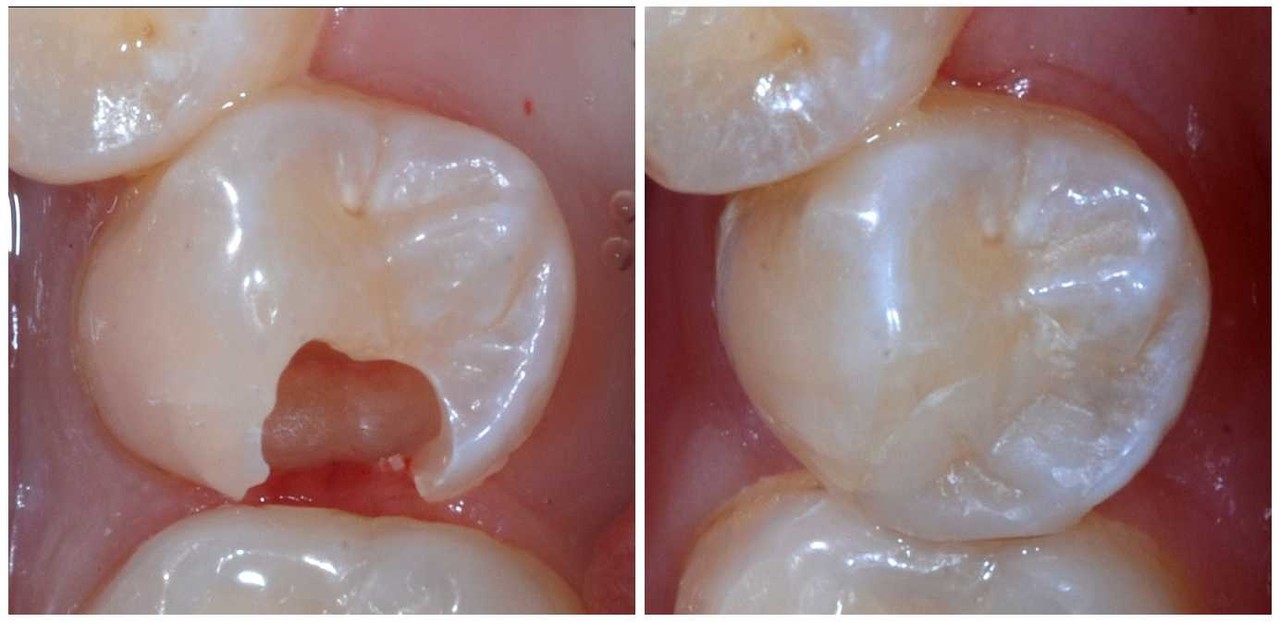

– Răng bị sâu nhẹ, sứt mẻ, mòn cổ răng

– Sau khi điều trị tủy, cần phục hồi thân răng